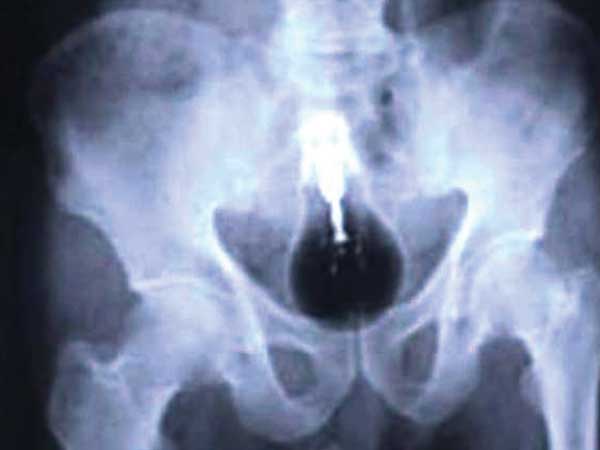

Light Bulb

Okay, it is true that a light bulb was found in the large intestine of a Pakistani prisoner. Now, you can let your imagination flow as to how did it even land there in the first place!